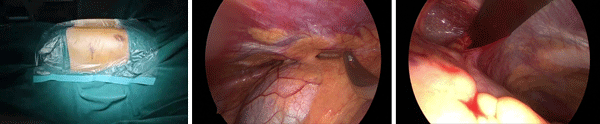

查体可见前胸壁凹陷,两侧胸壁向内收缩塌陷,左右胸廓对称,最深处位于“心口窝”上方,脊柱对称无侧弯。入院后科室经过详细术前讨论,考虑患者漏斗胸加重,出现胸闷、心悸等不适,并且畸形影响美观,对患者造成心理不适,同时患者本人手术意愿强烈,因此我们于2025年8月14日在全麻下给患者实施了微创胸腔镜漏斗胸矫正术(NUSS手术),手术历时2小时,过程顺利。于胸腔镜引导下精准置入矫形钢板,胸骨抬举满意,胸廓外形即刻得到改善。

术后未放置引流管,切口采用美容缝合,并予镇痛、雾化等综合治疗,患者恢复迅速。

手术中体位,矫形器置入过程